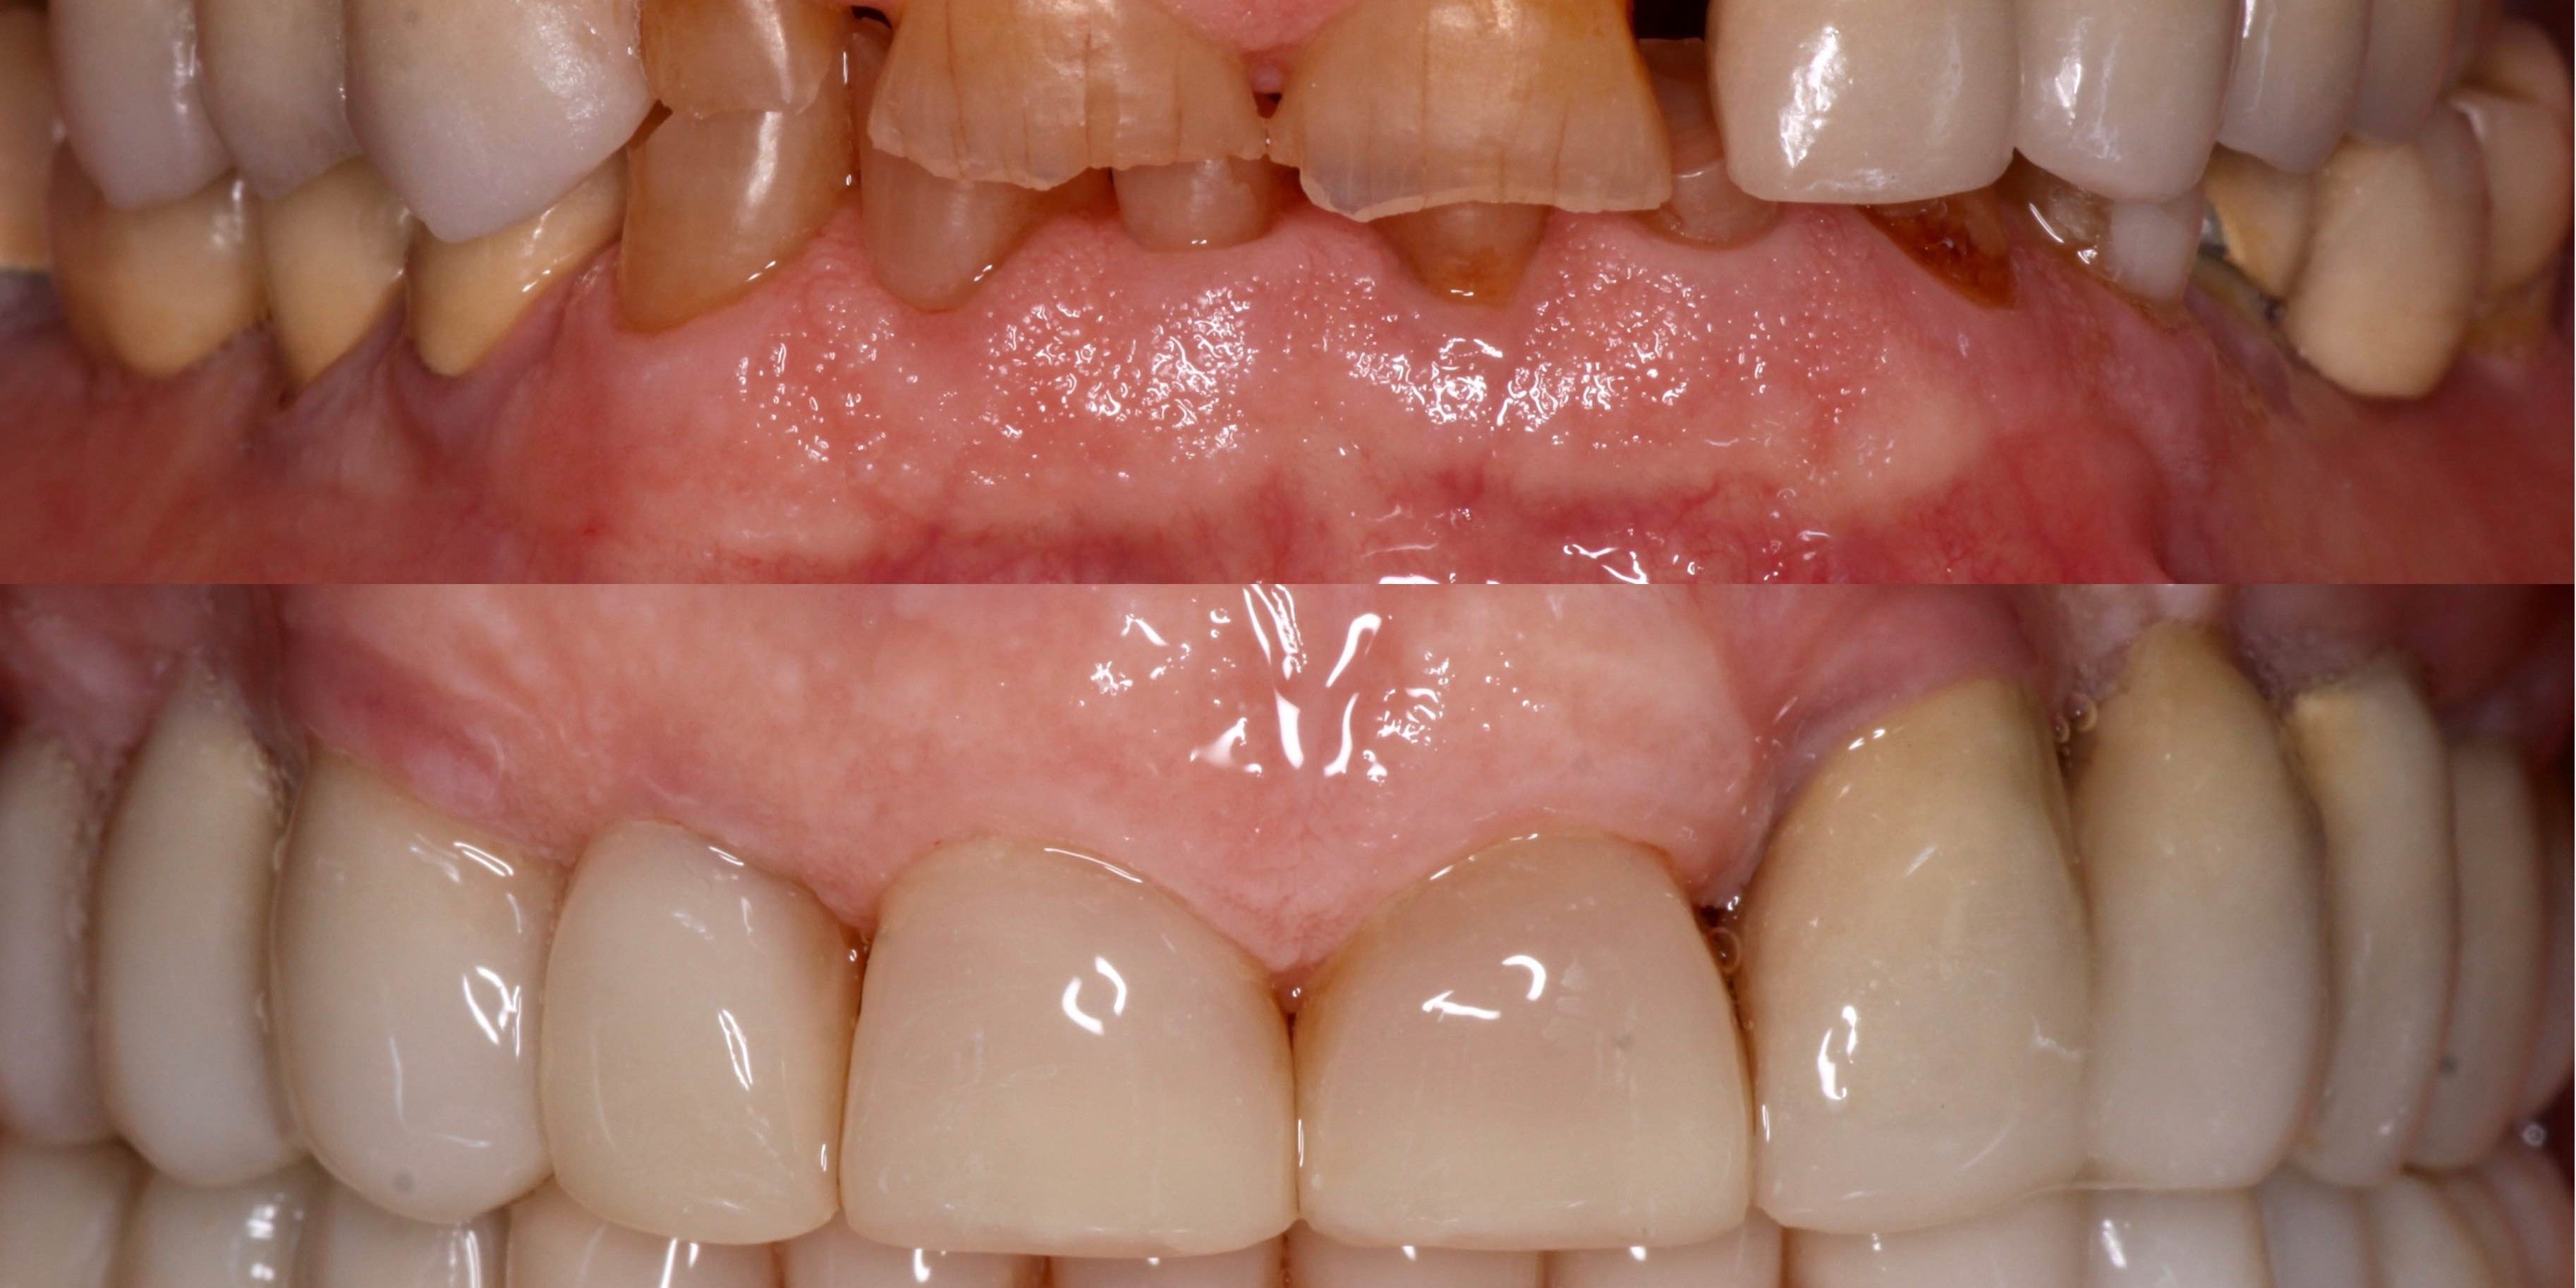

Paciente de 79 años acude a la consulta con gran destrucción dentaría y es portador de prótesis fija en zonas posteriores. Debido a la complejidad de remover todas sus prótesis a su edad y no dañar los pilares dentales se optó por hacer una rehabilitación mínimamente invasiva con composite. Los puentes suyos se mantuvieron en boca al comprobar que estaban en buen estado y se realizó un recubrimiento con composite de los mismos y de sus piezas naturales con destrucciones según las exigencias estéticas y funcionales, así como la colocación de implantes en zonas de ausencias dentales. el tratamiento tuvo unos 4 meses de duración. Posteriormente se colocó una férula de bruxismo de protección. El caso lo realizó conjuntamnte el Dr.Susín (parte rehabilitadora protésica y restauradora adhesiva) con el Dr.Plaza (colocación de los implantes)

- Intraoral Inicial

- Intraoral Final